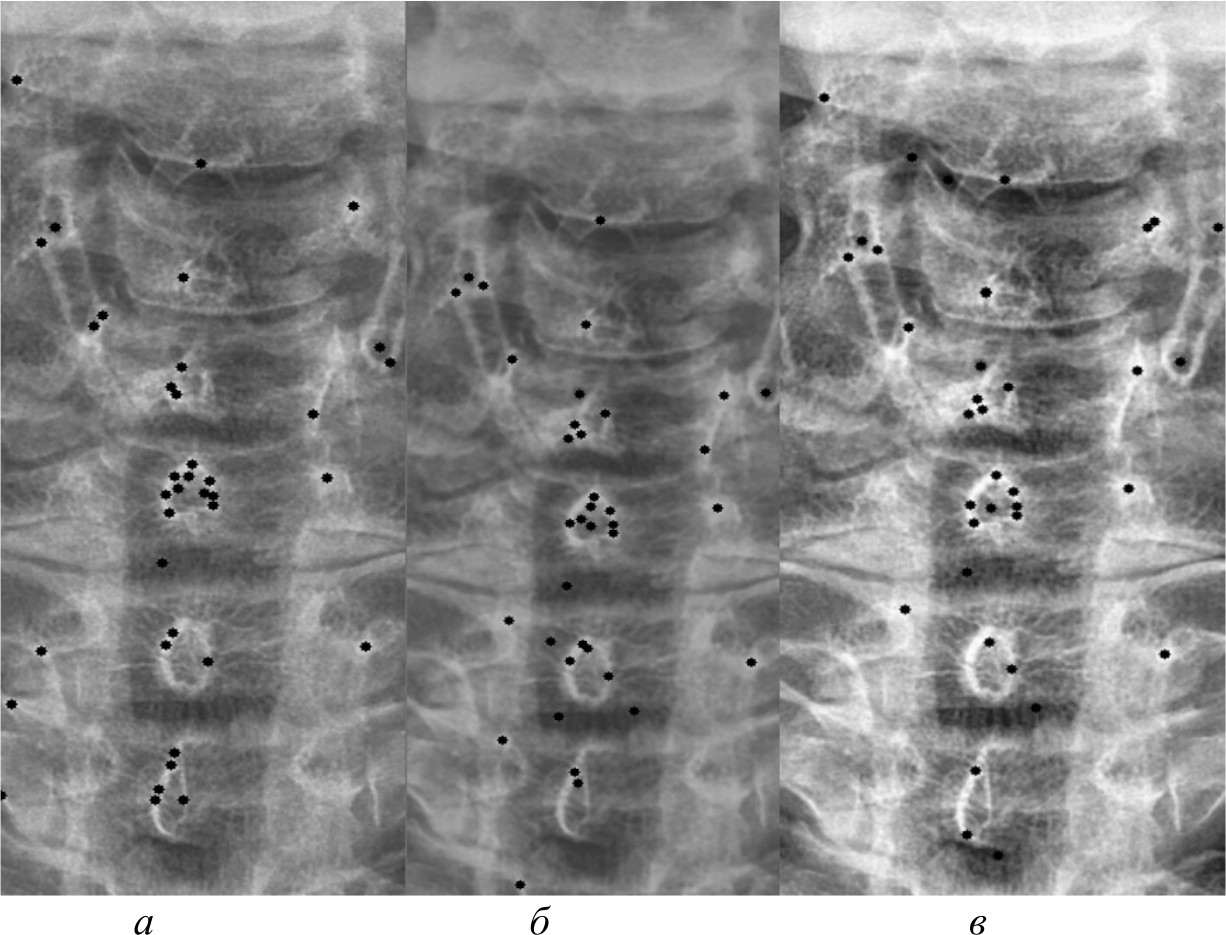

На рис. 4, 5 и 6 представлены результаты работы детектора Харриса, алгоритма Shi-Tomasi и SIFT при различных методах предварительной обработки изображений.

Рис. 4. Результаты работы детектора Harris на изображении, полученном при помощи специализированного программного обеспечения (а); результаты работы детектора Harris при методе адаптивной эквализации гистограммы (б); результаты работы детектора Harris при методе стандартной эквализации гистограммы (в); результаты работы детектора Harris при методе гамма-коррекции (г)

Рис. 5. Результаты работы алгоритма Shi-Tomasi на изображении, полученном при помощи специализированного программного обеспечения (а); результаты работы алгоритма Shi-Tomasi при методе базового отображения в Python (б); результаты работы алгоритма Shi-Tomasi при методе базового отображения Python с применением медианного фильтра (в); результаты работы алгоритма Shi-Tomasi при методе адаптивной эквализации гистограммы (г); результаты работы алгоритма Shi-Tomasi при методе стандартной эквализации гистограммы (д); результаты работы алгоритма Shi-Tomasi при методе гамма-коррекции (е)

Рис. 6. Результаты работы алгоритма SIFT на изображении, полученном при помощи специализированного программного обеспечения (а); результаты работы алгоритма SIFT при методе адаптивной эквализации гистограммы (б); результаты работы алгоритма SIFT при методе стандартной эквализации гистограммы (в)